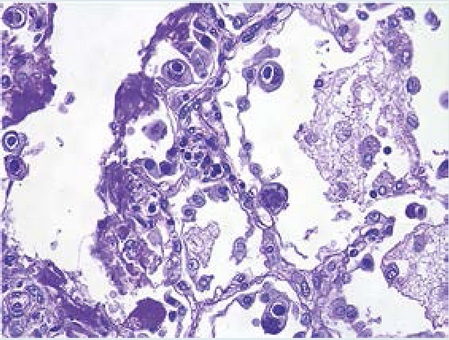

En la examinación histológica se observó una meningoependimocoroiditis piógena aguda (Figura 7) representada por un exudado supurativo con bacilos Gram negativos en ventrículos laterales, corroborada con el cultivo post mortem que reportó desarrollo de Pseudomonas aeruginosa en líquido cefalorraquídeo, pulmón, hígado y bazo. Los pulmones tenían una gran cantidad de macrófagos alveolares infectados por citomegalovirus (Figura 8). Además, se observaron cambios citopáticos virales por citomegalovirus en glándulas salivales, páncreas, suprarrenales, esófago, estómago, plexos coroides y médula espinal. Finalmente, se observaron datos anatómicos de choque: daño alveolar difuso en fase exudativa (membranas hialinas) con edema pulmonar agudo; miopatía visceral hipóxico-isquémica en corazón, tubo digestivo y vejiga; esteatosis hepática universal macro y microvesicular con colestasis leve; involución grave del timo (2 g vs. 20 g); dilatación vesical y dilataciones segmentarias del intestino delgado y colon sigmoides; nefromegalia bilateral (riñón izquierdo 65 g vs. 40 g, derecho 70 g vs. 44 g).